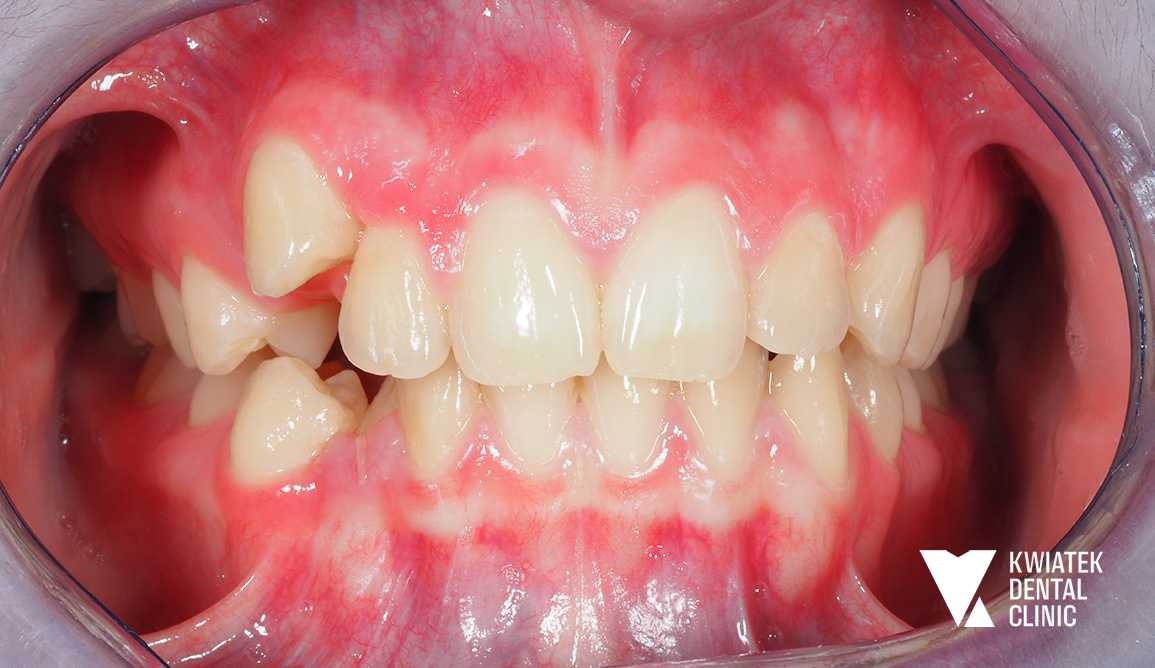

Pełna rekonstrukcja zwarcia i estetyki - historia wymagającej metamorfozy

Pacjent zgłosił się do kliniki z zaawansowanymi problemami stomatologicznymi: licznymi ubytkami próchnicowymi, brakami zębowymi, starciem zębów oraz zaburzeniami zwarcia. Leczenie obejmowało kompleksową diagnostykę, leczenie zachowawcze i endodontyczne, zabiegi chirurgiczne, implantację oraz wieloetapową odbudowę protetyczną. Efektem terapii jest perfekcyjnie zbalansowany zgryz, najwyższy komfort funkcjonowania oraz naturalnie piękny uśmiech, który podkreśla indywidualny charakter pacjenta i pozwala mu w pełni cieszyć się nim każdego dnia.